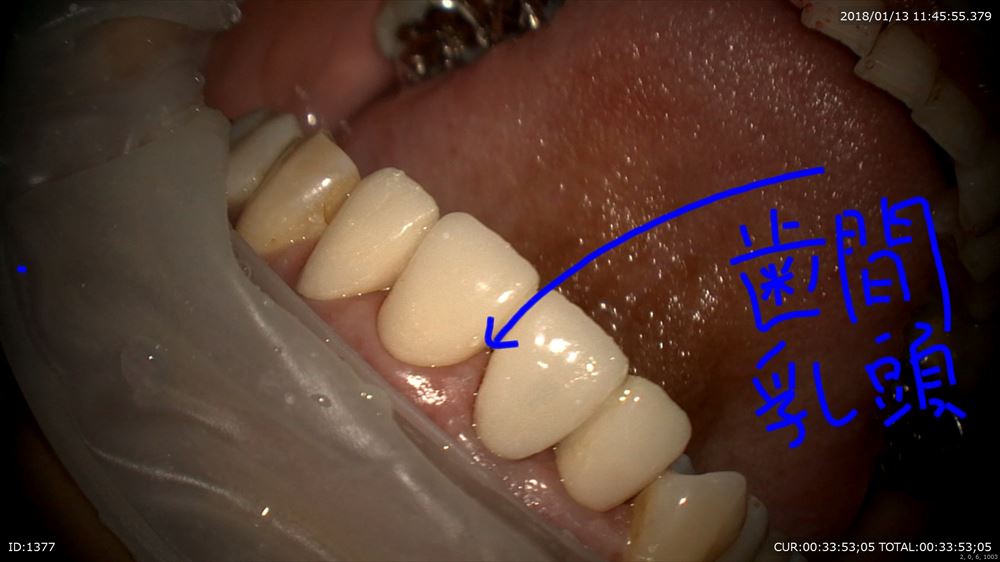

右上1番のインプラント歯茎の形態を仮歯で作ります。

マイクロスコープ治療で仮歯を調整。

エマージェンスプロファイルを調整。

仮歯完成!!インプラントの淵が見えなくなりました。あー緊張した。ここまで1年。患者さま喜んで頂けました。

ここからまた3ヶ月みて最終的な型をとります。前歯の治療ですので妥協は絶対ダメです。うちの技工士に怒られます。